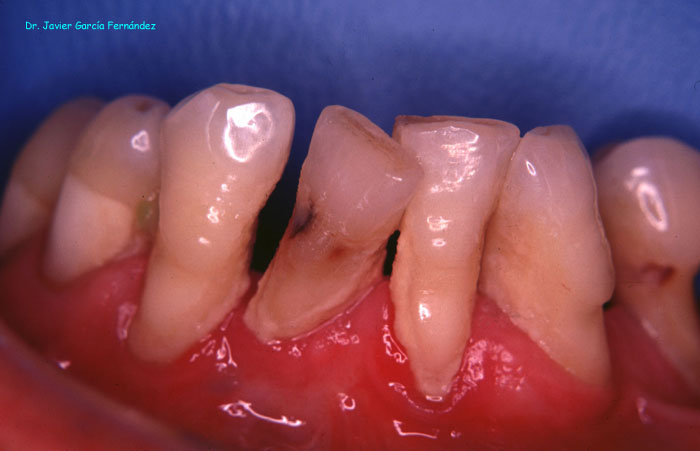

De la Salud a la Enfermedad Periodontal

image019